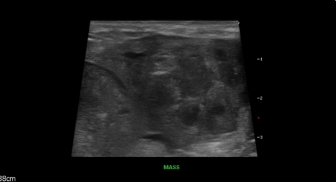

복부/심장 초음파 검사는 복강 내에 존재하는

장기들은 물론 혈관과 같은 작은 구조물,

심장의 움직임 및 구조까지 실시간으로

평가할 수 있는 비침습적인 검사입니다.

복부 초음파

소화기계 관련 증상, 비뇨기계 관련 증상,

간/담도계 관련 증상은 물론 신경증상이나 호르몬 질환이

의심될 경우에도 복부 초음파 검사가 지시될 수 있습니다.

비장종양

복부 소장이물